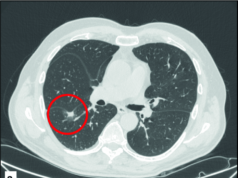

The most widely used imaging methods in oncology are based on ionising rays, making it undesirable to resort to these methods for screening and for frequent disease monitoring, especially in young patients and women of fertile age. Since its introduction, magnetic resonance imaging has developed surprising abilities to distinguish between normal and tumour tissue without unwanted effects. Diffusion sequences reflect the restricted mobility of water protons that occurs in some tumours because of their greater cell density. The consequent increase in contrast between tumour and normal tissue allows spatial localisation of the cancer. The increased sensitivity and specificity of diffusion-weighted WB-MRI has been demonstrated in cancer patients, but the data on healthy subjects are still preliminary. The possibility of diagnosing cancer in the 1–2% of asymptomatic subjects who undergo screening DWB-MRI makes this test interesting, although findings calling for further investigation may be produced in as many as 30% of those screened, according to published data.